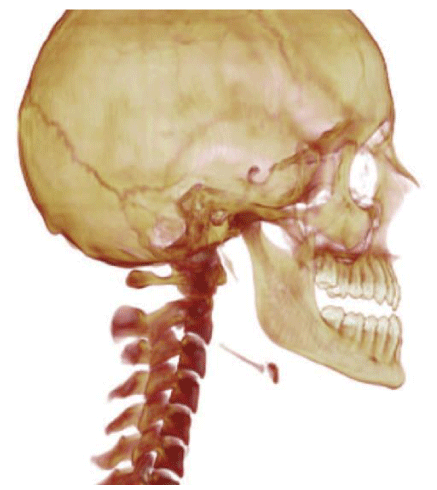

Nineteen consecutive patients previously treated for their temporomandibular pathologies were studied by CBCT images and Dolphin Imaging Software 11.7, permitting the Second Phase of the treatment [Figure 1,2].

TMJ pre-orthodontic, cephalometric and routine tests were indicated. Patients were informed about procedures and consented to the present study. In the differential diagnosis of temporomandibular joint pathology, age and sex were not significant for this investigation. A total of 38 joints were evaluated as independent units [Figure 3a,b,c].